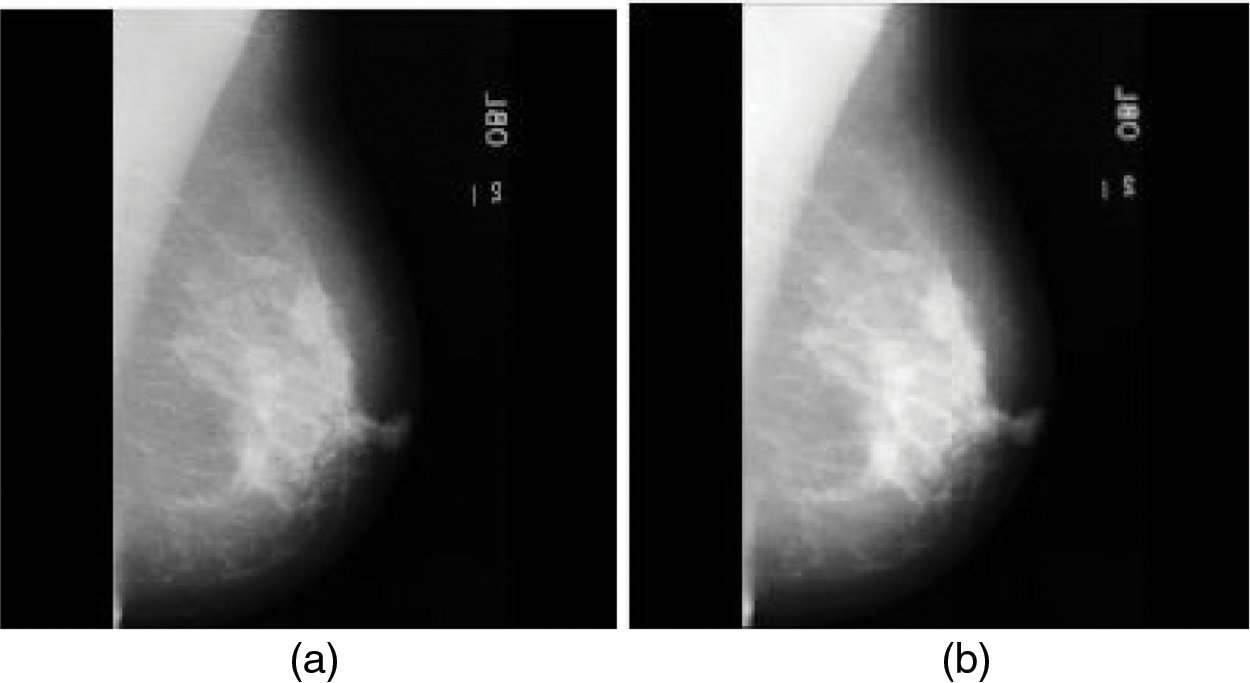

Cancer is a crucial disease in women around the world which causes death. Timely and early detection of cancer can save the life of women patients. Most cancer causes deaths in women patients are categorized into breast and cervical. When compared with the death history of women patients due to cervical cancer, breast cancer is the most dangerous and life-threatening disease [1–3]. Breast cancer can be screened by two different methods as Histopathology and mammogram. The histopathology method finds the abnormality of the nucleolus of the breast cells. This method is cost expensive and the breast cancer detection accuracy is low. These limitations are overcome by screening and inspecting the cancer regions in mammogram images. Bypassing the low-intensity and low-profile laser beam through the breast cells in breast, mammogram images are obtained [4]. Breast cancers are categorized into benign and malignant based on the size of the cancer regions. The benign is low-spreading cancer and its spreading ratio is low when compared with other types. Malignant is high-spreading cancer and its spreading ratio is high when compared with the benign type. It is very important to detect both benign and malignant for further breast cancer diagnosis process. Fig. 1a shows the normal mammogram case, in which there are no suspect mass regions. Fig. 1b shows the abnormal mammogram case which is known as benign. In this case, the nerves are starting to damage. Fig. 1c shows the abnormal mammogram case which is known as malignant. In this case, the nerves are starting to damage very fast when compared with benign. Breast cancer diagnosis includes correctly identifying each stage and classifying detected breast tumors and abnormalities into proper categories. To assist radiologists and oncologists in diagnosing breast cancer in a fast and reliable manner, many Computer-Aided Diagnosis (CAD) systems have been developed over the last two decades [2]. Unfortunately, earlier CAD systems did not produce significant improvements in day-to-day breast cancer diagnosis in clinical use [3,4]. After the ‘boom’ of deep learning (DL), DL-based CAD systems and other computer vision and object recognition methods brought success to many areas of medicine, from day-to-day healthcare practices to comprehensive medical applications [5–9]. Currently, many DL-based CAD systems can be used to assist radiologists in breast cancer screening, monitoring, and diagnosis.

Figure 1: Mammogram images (a) Normal case (b) Benign case (c) Malignant case (Novitasari et al. 2019)